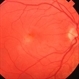

- subfoveal CNVM

- subfoveal choroidal neovascularization

- Fundus photograph of left eye of 65-year-old lady with large subfoveal CNVM